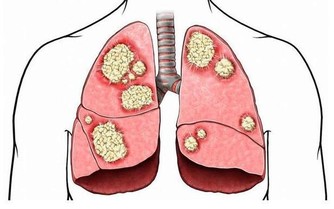

紅辣椒花椒水

功效:淤積濕寒的風濕性關節炎

1、干紅辣椒25 個,花椒30 克。

2、花椒加水3000 毫升,文火煎半小時,放入紅辣椒煮軟取出,去籽。

3、將辣椒皮撕開,貼於患處,共貼三層(可用紗布綁住),敷10 分鐘左右(可根據自己的忍耐程度縮短敷治的時間)。

4、每晚敷1 次,連敷1 週。

注:連續用的花椒水中,放入的辣椒皮必須每次更新。